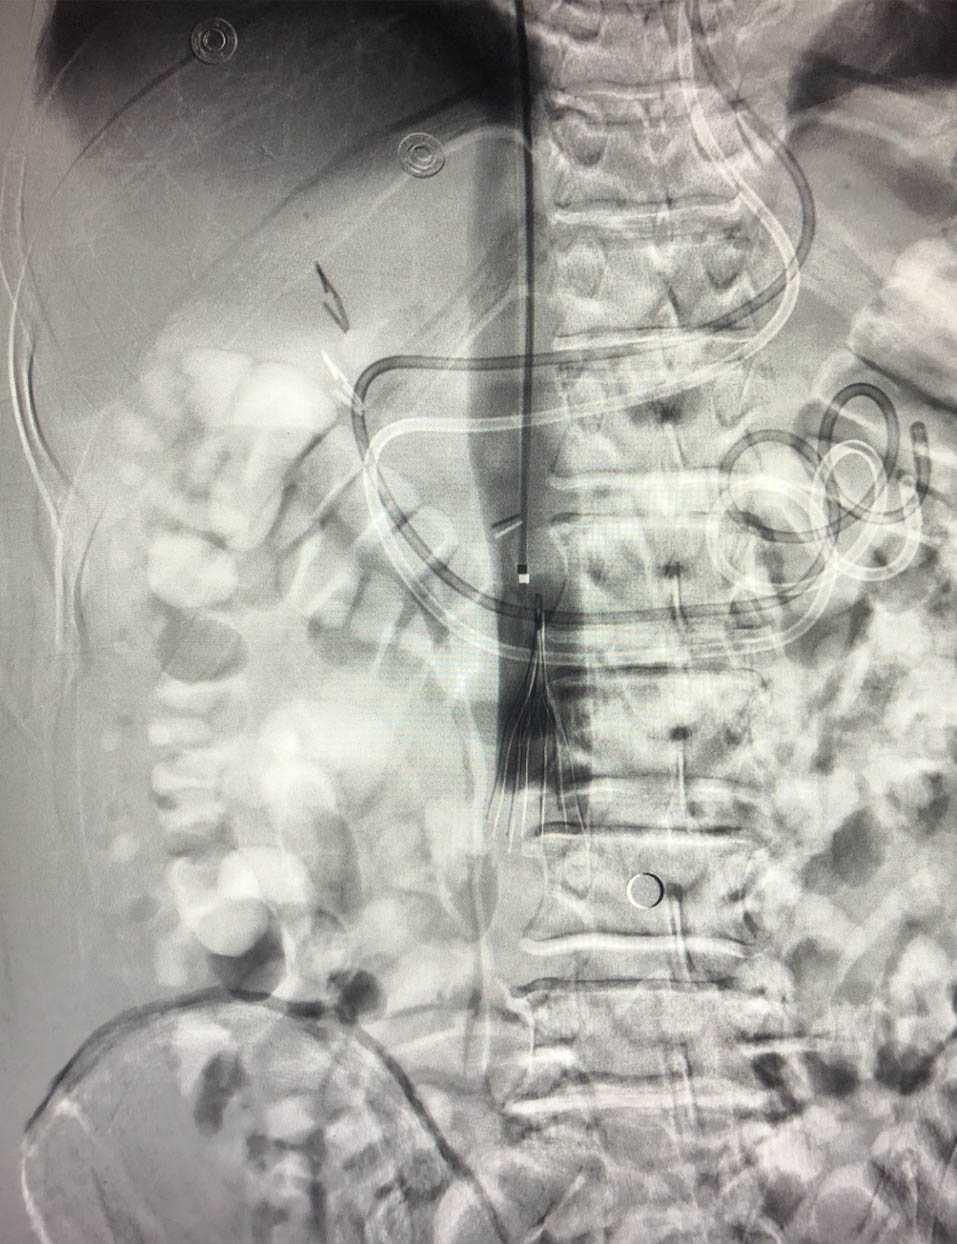

ECMO运行24 h后患者VTI 20.4 cm,EF 55%,右心功能良好,室壁运动协调,导致患者本次心搏骤停的原发病肺栓塞经肺动脉吸栓术后已解除,患者进入撤机流程(视频1见网站附录)。ECMO撤机后患者神经功能完全恢复(视频2见网站附录),呼吸循环稳定。撤机1 d予复查CTPA,提示两侧肺动脉远端血供再通(图 3)。复查双下肢深静脉超声,提示左股静脉及腘静脉内血栓,考虑血栓较大且新近形成,脱落风险大,予介入放置下腔静脉滤网(图 4),并经Angiojet导管吸除股静脉及腘静脉血栓。

| 图 4 下腔静脉放置滤网 |